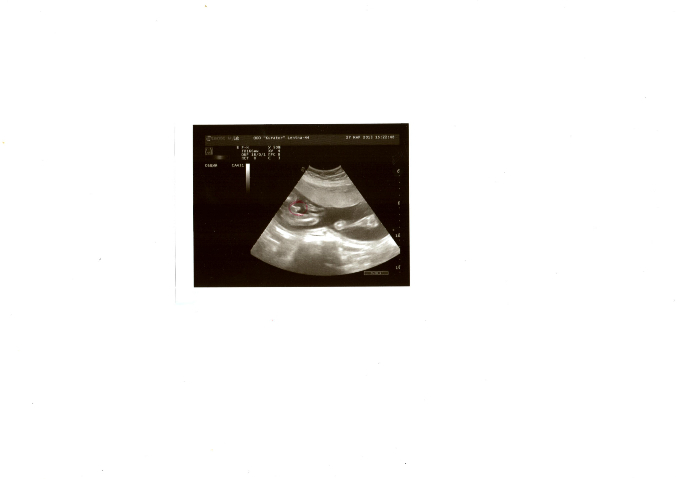

узи в 22 недели......

Вопросы про УЗИ, обследования и анализы: что, где, как, когда?Сегодня сходила на узи.Увидала своего сыночка!Весь крутится и руками машет,смешной мой......Опять у нас тонус,и видимо в момент узи был и сначала врачу не понравился мой приоткрытый зев,у меня чуть ли не паника,но под конец узи он сомкнулся.моя гиня говорит,это из за тонуса бывает,...Короче не хотела я ,но посадила она меня на гинипрал,для снятия тонуса.......................Хотели сделать фото,но сынок так крутился и ничего путного не выходило,но самое главное поймали мы наш писюнчик(в красном кружке)